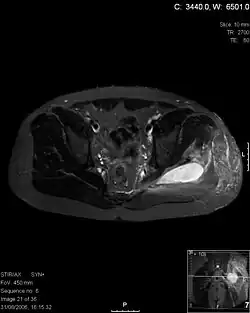

![]() | |

| Transverse T2 magnetic resonance imaging section through the hip region showing abscess collection in a patient with pyomyositis. | |